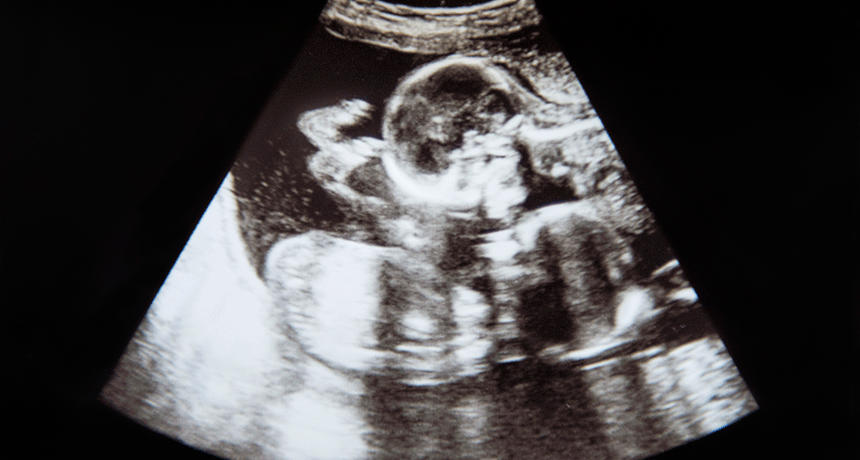

This is an ultrasound image from inside a pregnant woman’s uterus. If you look carefully, there’s not one baby in there, but two! This woman was pregnant with twins.

BorupFoto/iStockphoto

It is more common, though, to see the term “ultrasound” in medicine. When a doctor wants to see what’s going on inside a patient, one option is ultrasound. She can use a device that will send these ultra-high frequency sound waves into the patient’s body. The sound waves bounce off whatever is inside. The machine reads the echoes of those waves as they come out of the body. Then it uses those echoes to create an image of anything inside, such as internal organs, a tumor or a baby.